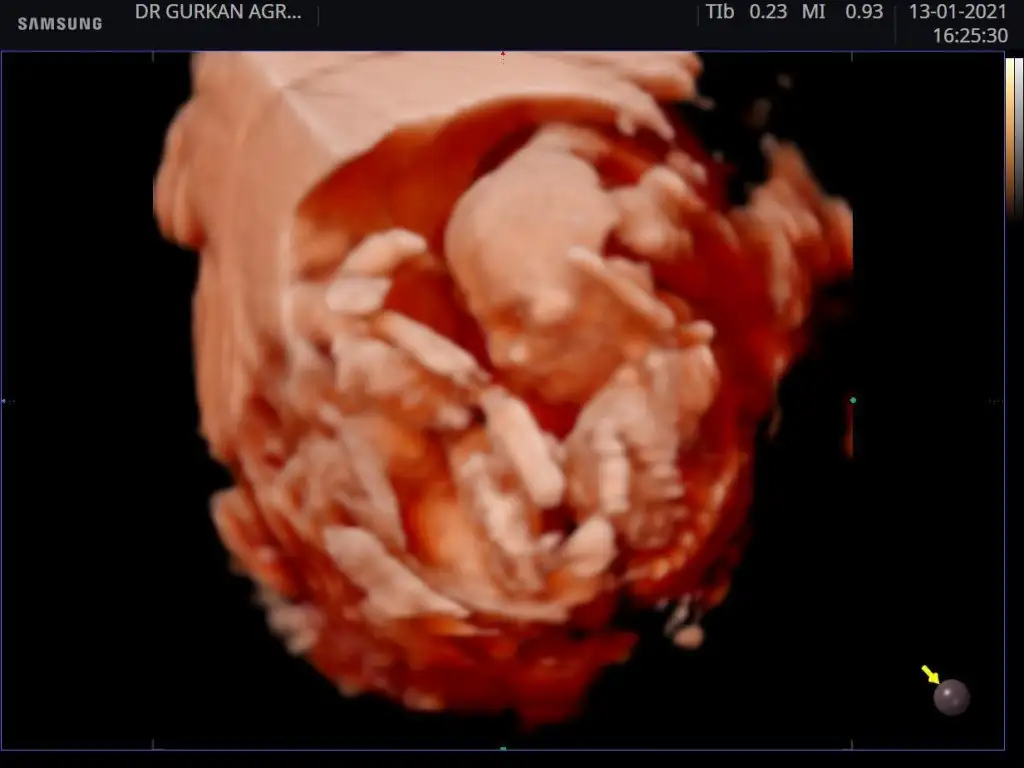

Hayirli sağlıklı olsun.dr mu soyledi.usg paylasmistin degil mi burada.gelecegi parlak cok sansli olsun bebegin.Benim ki. Kız kesin

Evet Dr söyledi teşekkürlerHayirli sağlıklı olsun.dr mu soyledi.usg paylasmistin degil mi burada.gelecegi parlak cok sansli olsun bebegin.

Ben de kız demistim .o haftalik ultrason kaginda daha belli oluyor cinciyet tahmini.çıkınti paralel oldugu icin kız demistim ben de.buradaki fotoda net belli sizin.seni çok iyi anlıyorum.benim de iki kızım var.ve ücuncuyu istiyoruz.olmadi 5 aydir gebelik.hayırlısı olsun.saglikli olsun en önemlisi.Rabbimin vardır bildiği .verdiyse en hayırlısını vermistir.gönlünü ferah tut .Evet Dr söyledi teşekkürlerEki Görüntüle 2764435

Ama çoğu kişi erkek bu bebek diyorBen de kız demistim .o haftalik ultrason kaginda daha belli oluyor cinciyet tahmini.çıkınti paralel oldugu icin kız demistim ben de.buradaki fotoda net belli sizin.seni çok iyi anlıyorum.benim de iki kızım var.ve ücuncuyu istiyoruz.olmadi 5 aydir gebelik.hayırlısı olsun.saglikli olsun en önemlisi.Rabbimin vardır bildiği .verdiyse en hayırlısını vermistir.gönlünü ferah tut .

Ben de kız demistim .o haftalik ultrason kaginda daha belli oluyor cinciyet tahmini.çıkınti paralel oldugu icin kız demistim ben de.buradaki fotoda net belli sizin.seni çok iyi anlıyorum.benim de iki kızım var.ve ücuncuyu istiyoruz.olmadi 5 aydir gebelik.hayırlısı olsun.saglikli olsun en önemlisi.Rabbimin vardır bildiği .verdiyse en hayırlısını vermistir.gönlünü ferah tut .

Ben cizmedim isegramdan bu sayfa çizdi cinsiyetini öğren diye bi sayfaSen ustunu cizmissin bilemedim simdi.baska bir dr a da gitsen imkanın vaktin varsa için rahat olur .

Evet o sayfa bana erkek dedi bugün öğrenmeye gideceğim bende hayırlısı olsunBen cizmedim isegramdan bu sayfa çizdi cinsiyetini öğren diye bi sayfa